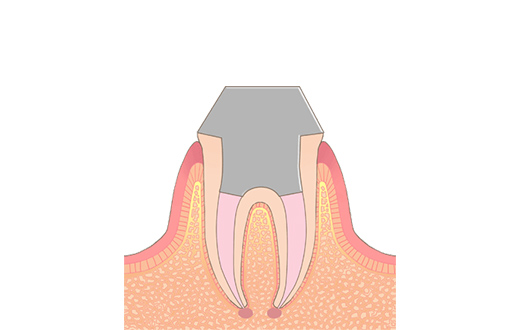

STEP05コア形成・印象

神経が入っていた部分は全て取り除かれ、お口の中に見えている頭の部分は空洞になっているので、その空洞を埋める土台の型取りを行います。

場合によっては、直接その空洞を埋める処置を行うこともあります。型取りをした場合は、後日土台を装着し、被せ物の型を採ります。 -